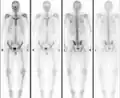

The radiographic appearance of osteopoikilosis on an X-ray is characterized by a pattern of numerous white densities of similar size spread throughout all the bones. This is a systemic condition. It must be differentiated from blastic metastasis, which can also present radiographically as white densities interspersed throughout bone. Blastic metastasis tends to present with larger and more irregular densities in less of a uniform pattern. Another differentiating factor is age, with blastic metastasis mostly affecting older people, and osteopoikilosis being found in people 20 years of age and younger.

The distribution is variable, though it does not tend to affect the ribs, spine, or skull.[2]